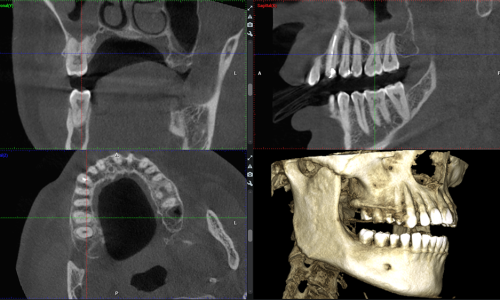

Radiologia Odontoiatrica Digitale 3D

L’imaging dentale viene ottenuto utilizzando l’innovativo TC Cone Beam Planmeca Viso G5, per l’altissima qualità delle immagini e per il comfort e la sicurezza del paziente. Possiamo acquisire una panoramica 2D delle arcate dentali e anche delle immagini 3D straordinariamente realistiche, effettuando immagini paragonabili ad una Tac tradizionale, ma con dose radiogena molto inferiore grazie al sistema Ultra low dose.

La sicurezza del paziente è un valore molto importante per OPTIMUM, così come effettuare l’esame in modo veloce e confortevole: il posizionamento del paziente è facile, il viso non è ingabbiato, ha solo un comodo supporto occipitale che garantisce la stabilità. Anche se il paziente dovesse muoversi, ad esempio un bambino o un anziano con patologie, l’immagine sarà chiara e dettagliata, grazie all’algoritmo di correzione degli artefatti da movimento e grazie alla velocità dell’acquisizione.

TC Cone Beam Planmeca Viso G5

Questa apparecchiatura innovativa è utilizzabile per tutti i tipi di indicazioni, ad esempio per valutare la vicinanza dei denti del giudizio ai nervi alveolari inferiori, la quantità ossea per il posizionamento di impianto, i disturbi dell’articolazione temporo-mandibolare, la patologia ossea nelle mascelle, le lesioni traumatiche al viso e le deformità dentofacciali.

La nuova modalità di acquisizione immagini endodontiche 3D per le unità Planmeca Viso permette l’acquisizione di immagini CBCT nitide e uniformi, ideali per l’endodonzia.

Con il paziente si possono condividere le immagini 3D acquisite digitalmente, con la possibilità di vedere le articolazioni, le vie aeree e la posizione dei denti, dal singolo dente al telecranio.